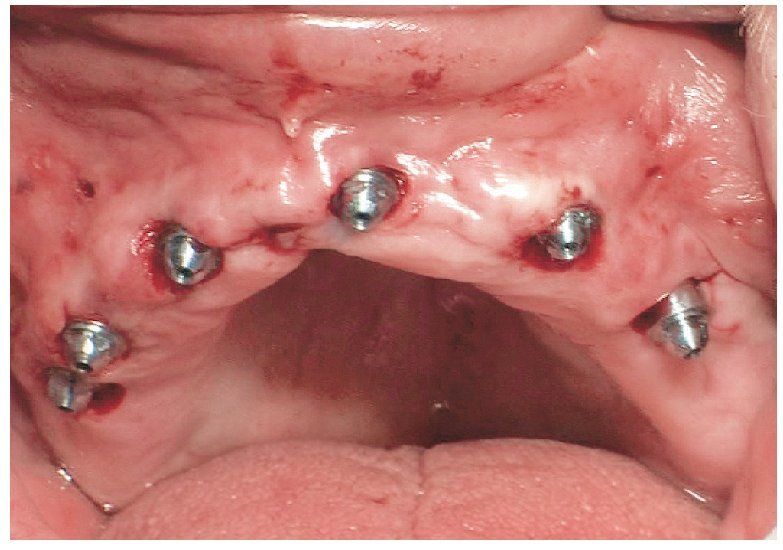

Fig. 69. Los implantes y las cofias provisionales para prótesis atornilladas colocados en el maxilar inferior.

La intervención quirúrgica (figs. 63 y 64) se realizó bajo anestesia local y se trataron al mismo tiempo ambas arcadas dentarias. Durante la primera fase se insertaron seis implantes cónico-cilíndricos (SPI®CONTACT, Thommen Medical AG, Waldenburg, Suiza) en la arcada dentaria superior mediante un acceso sin colgajo. Para ello se utilizaron los pilares pertinentes para reposiciones de puente atornilladas oclusalmente (VarioMulti, Thommen Medical AG, Waldenburg, Suiza) (fig. 65). Tras la intervención quirúrgica se colocó en boca la prótesis provisional prefabricada a partir de los datos de planificación y tallada en las posiciones de implante y se unió a las cofias provisionales (fig. 66 y 67); para ello se utilizó un composite de fraguado dual. Mediante una prótesis provisional mucosoportada se pudo preservar la estructura gingival hasta el momento de la implantación, y con ello la relación correcta entre los maxilares superior e inferior. Para la arcada dentaria inferior se utilizaron implantes cilíndricos (Element, Thommen Medical AG) (figs. 68 y 69). En combinación con los pilares pertinentes para prótesis atornilladas, se procedió aquí de la misma manera que en el maxilar superior. Una vez se hubo alineado oclusalmente la prótesis provisional del maxilar inferior con respecto al superior, se fijó sobre las cofias provisionales (fig. 70); debido a la formación de colgajo no había sido posible la alineación sobre la mucosa. Este procedimiento permite preservar la dimensión oclusal vertical que se definió al principio del tratamiento. A continuación se repasan, se pulen y se envían a la clínica para su incorporación las prótesis provisionales, las cuales, por el contrario, se apoyan exclusivamente sobre los implantes (figs. 71 y 72). Allí tienen lugar el control radiológico y el rectificado oclusal (figs. 73 y 74).